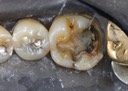

Kyle Chock #15 prep